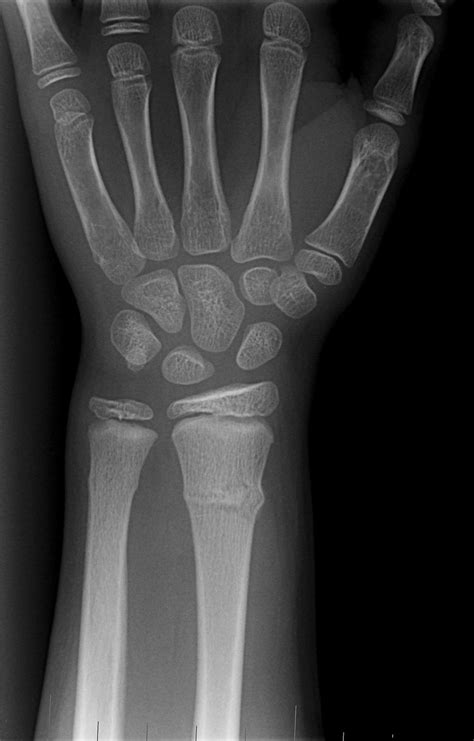

A broken hand, often diagnosed through an X-ray, involves a fracture in one or more of the bones in the hand. The hand is composed of 27 bones, including the metacarpals, phalanges, and carpals. Each of these bones can be susceptible to fractures, which can range from minor cracks to severe breaks.

• X-rays: X-rays are the primary imaging tool used to confirm the presence and type of fracture. They provide detailed images of the bones and can help determine the severity of the injury.

Carpal Fractures Fractures in the carpals, which are the small bones of the wrist. Falls onto an outstretched hand, sports injuries, or direct impact.